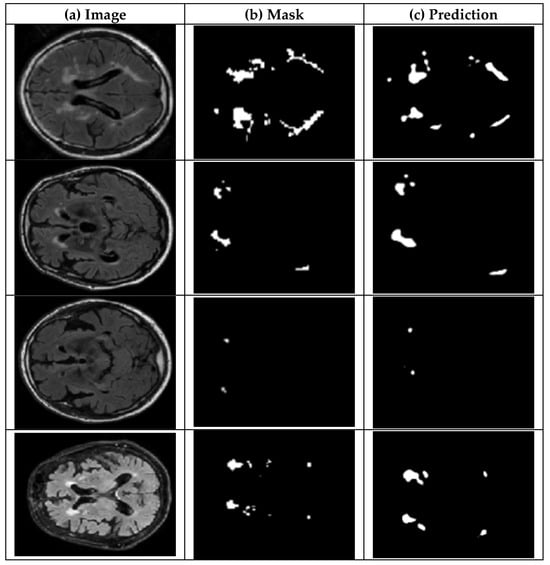

4.2.1. UNet Segmentation

4.2.2. SAM Model